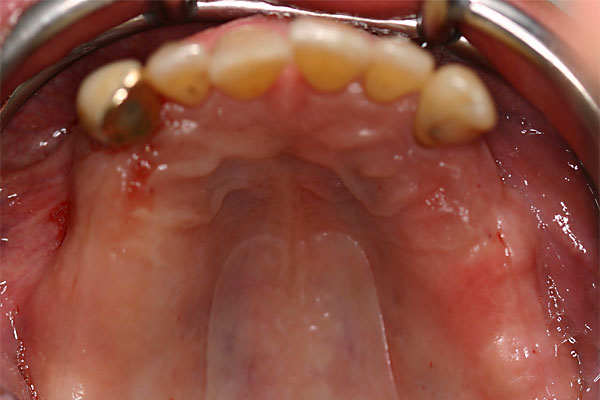

Fall: festsitzender Zahnersatz im Oberkiefer auf 8 Implantaten

FOTO Totale Prothese im Oberkiefer – Anfangsbefund |